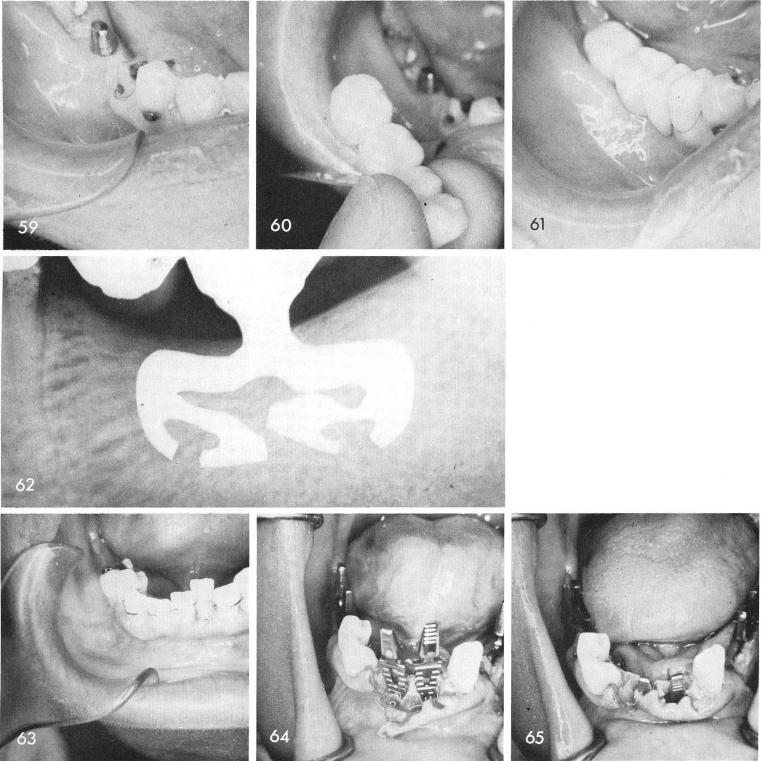

Wherever abutment teeth must be helped by further support other than the fixed bridge itself intra-tooth bladevents serve the purpose exquisitely, figs. 59, 60, 61. Notice in this nine year post-operative film that the originally broken blade (because of probably too shallow a groove and too hard tapping) caused no further bone damage, fig. 62.

Periodontally involved teeth that were over retained with wiring are often removed completely with immediate insertions of blades. These can go much deeper into the great depth of bone that exists in the symphyseal region than were the original teeth, thus aiding in the overall retention of the remaining weak teeth, figs. 63, 64, 65.